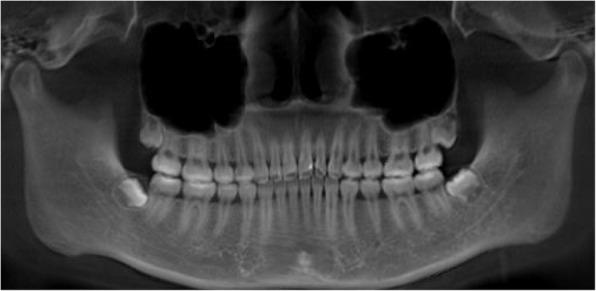

This study analyzed 27 patients (mean age 21.1 ± 4.9 years; 18 women, 9 men) who underwent extraction with clear aligners. In total, 54 maxillary lateral incisors were included-each patient contributed two teeth. CBCT scans were obtained at pretreatment and refinement. The projection of the midpalatal suture on the panoramic image helped measure the axial angulation of the maxillary lateral incisors. Three-dimensional reconstruction was performed using Mimics, and the maxillary structure superimpose method was employed to measure the horizontal distance of the maxillary lateral incisors. Influencing factors, including lateral incisor attachment, lateral incisor horizontal movement distance, upper dentition retraction method, and lateral incisor crown-to-root ratio, were analyzed. P < 0.05 was considered statistically significant.